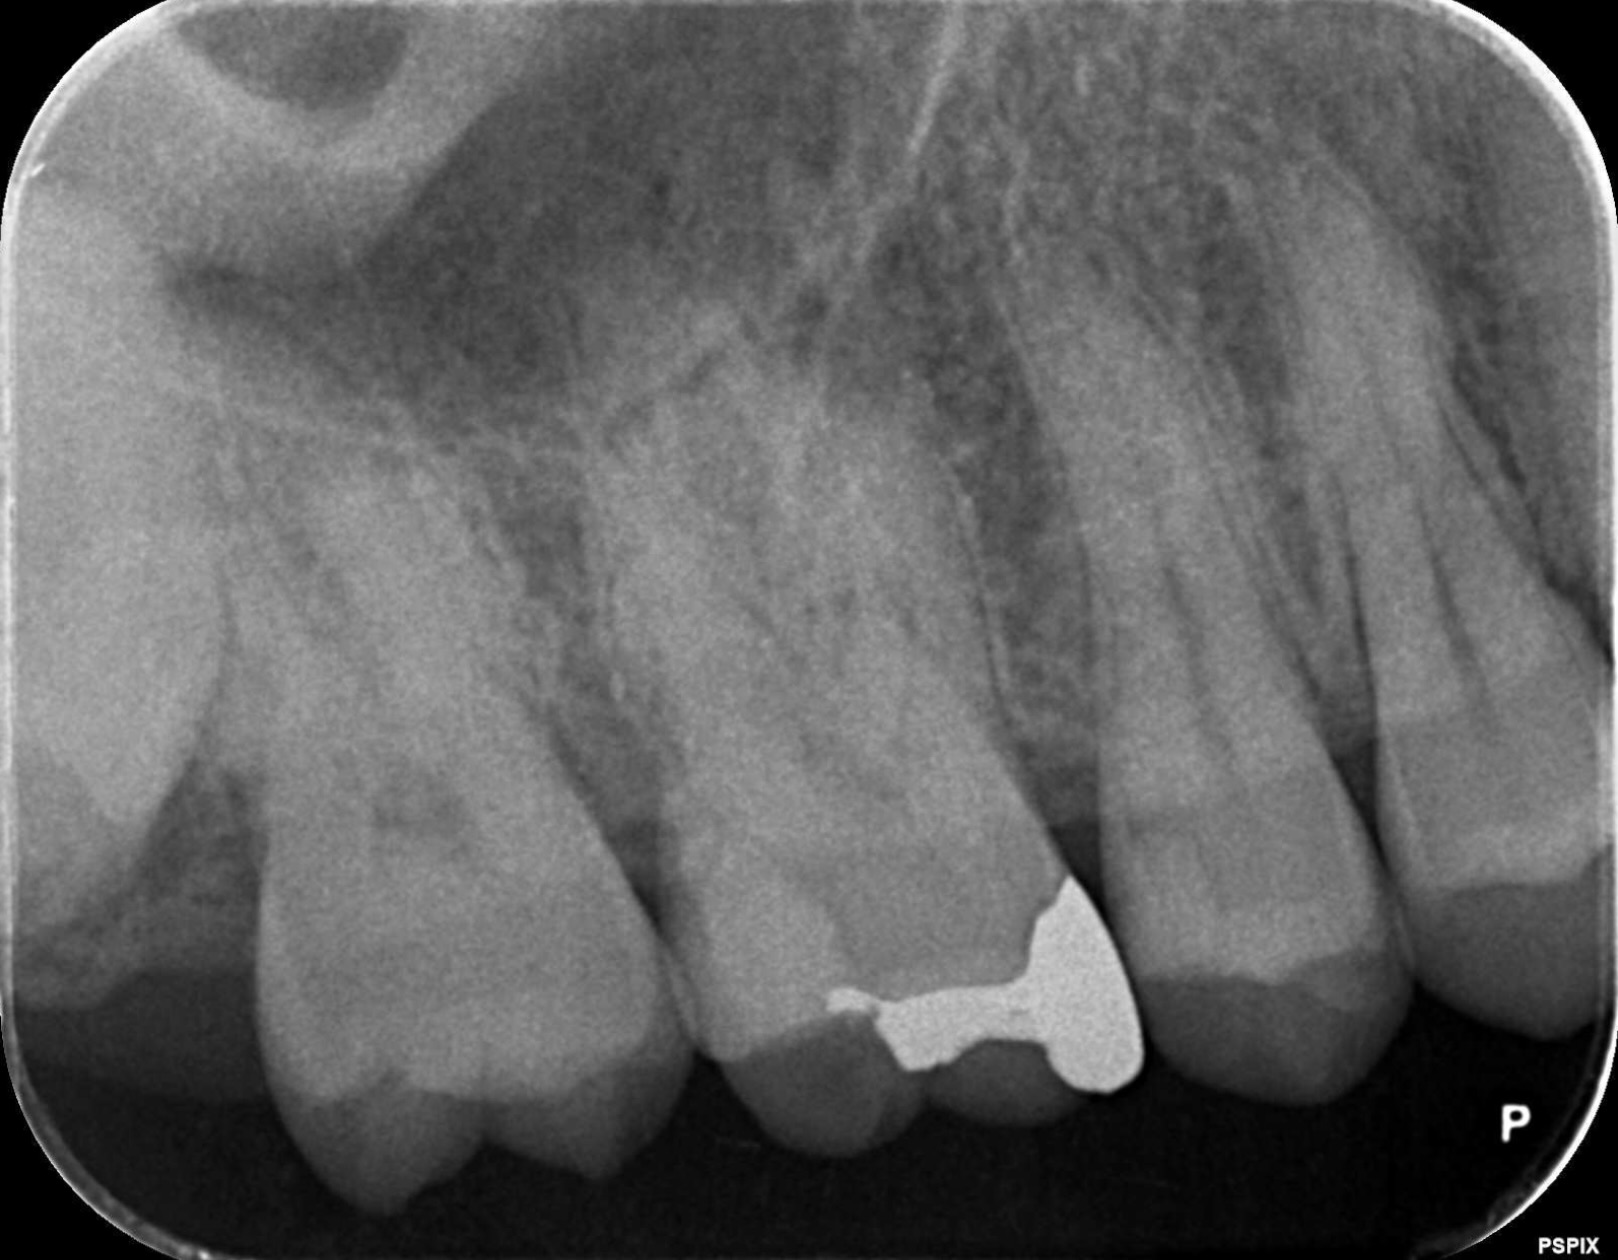

術後

術後レントゲン 術後口腔内

精密根管治療により感染源を除去。症状は消失し、機能的にも問題なく経過しております。